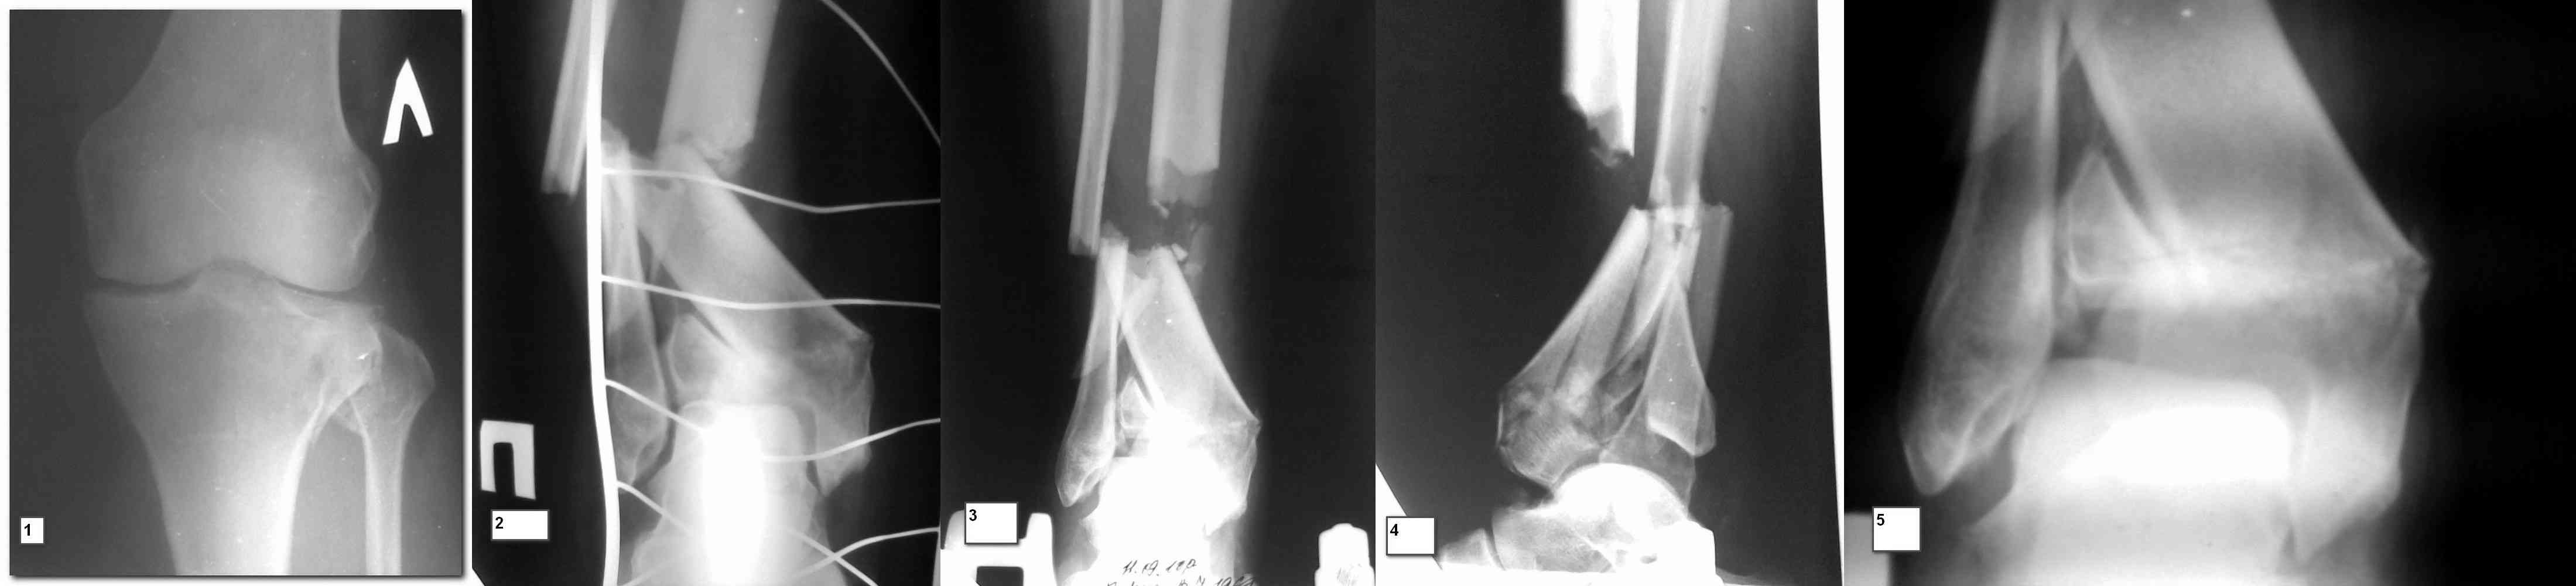

Вчера выполнена закрытая репозиця малоберцовой кости, промежуточный отломок расклинен с дистальным метаепифизом, выведен ближе к оси центрального отломка, вилка голеностопного сустава стала нормальной конфигурации, уменьшен вес вытяжения. Снимки представлю завтра.

На будущей неделе планируем открытую репозицию внешнего мыщелка левой б/б кости с костной пластикой и фиксацией пластиной. Открытая репозиция малоберцовой, синтез 1/3 пластиной, открытая репозиция сустаной поверхности, синтез, и тут проблема - в имеющихся в наличии пластинах нет необходимой длины для фиксации-мост к центарльному отломку. Как поступить? АВФ?

Снимки до и после закрытой репозиции

Как всегда прекрасная презентация. Совершенно согласен с необходимостью сохранять мениск и вообще согласен со всем, кроме одного. Фиксация должна проводиться после правильно выполненной репозиции. Главная цель репозиции - это восстановить высоту наружного мыщелка. В норме наружный мыщелок выше внутреннего на 4-5 мм на снимке в переднее заднем направлении АР.

Необходимость репозиции возникает при снижении высоты от 3 до 5 мм по разным источникам. По моему опыту 4 мм. Если не восстановить высоту мыщелка возникает вальгизация коленного сустава с относительным расслаблением передней крестообразной связки. При этом развивается нестабильность коленного сустава из-за недостаточности ПКС.

На представленном после операционном снимке нет репозиции, на что указывает низкое положение тибиального плато и перекрытие кортикальных пластинок в метафизарной части - указано стрелкой. Обычно чрескожную фиксацию я применяю

Пациентки прооперирована, результат чего на снимках. Выполнена открытая репозиция костей правой голени, синтез малоберцевой пластиной, б/берцевой винтами, имеющиеся фиксаторы не подходили, было принято решение репонировать отломки, синтез винтами, гипсовая повязка.

Мыщелок левой б/б кости репонирован закрыто, на контрольной рентгенограмме репозиция удовлетворительная, фиксировано спицами. гипсовая повязка.

Репозиция внутрисуставных переломов неудовлетворительная и не адекватна.

Сделайте снимок голеностопа контрлатеральной стороны, перенесите контур сустава на кальку и наложите её на свои послеоперационные Ргграммы - вам станет ясно что нужно сделать и какого стояния отломков достичь. Аналогичный

сценарий и для перелома наружного мыщелка б.б.- передний фрагмент стоит на месте, а задний не репонирован - в таком положении оставлять фрагменты нельзя, суставная поверхность должна быть реконструирована.

В лечении переломов пилона восстановление длины малоберцовой является индикатором и ориентиром для успешного лечения. Первый этап восстановления по длине не удался, малоберцовая остается короткой, и репозиция суставной поверхности осталась неудовлетворительной. Длина передней колонны не восстановлена, а в дистальном фрагменте имеется флексия. Оставлена без внимания потеря кости в метафизе. Шурупы 4.5 мм будут выступать после спадения отека, и возможно будут причиной мягкотканого осложнения в гипсе.